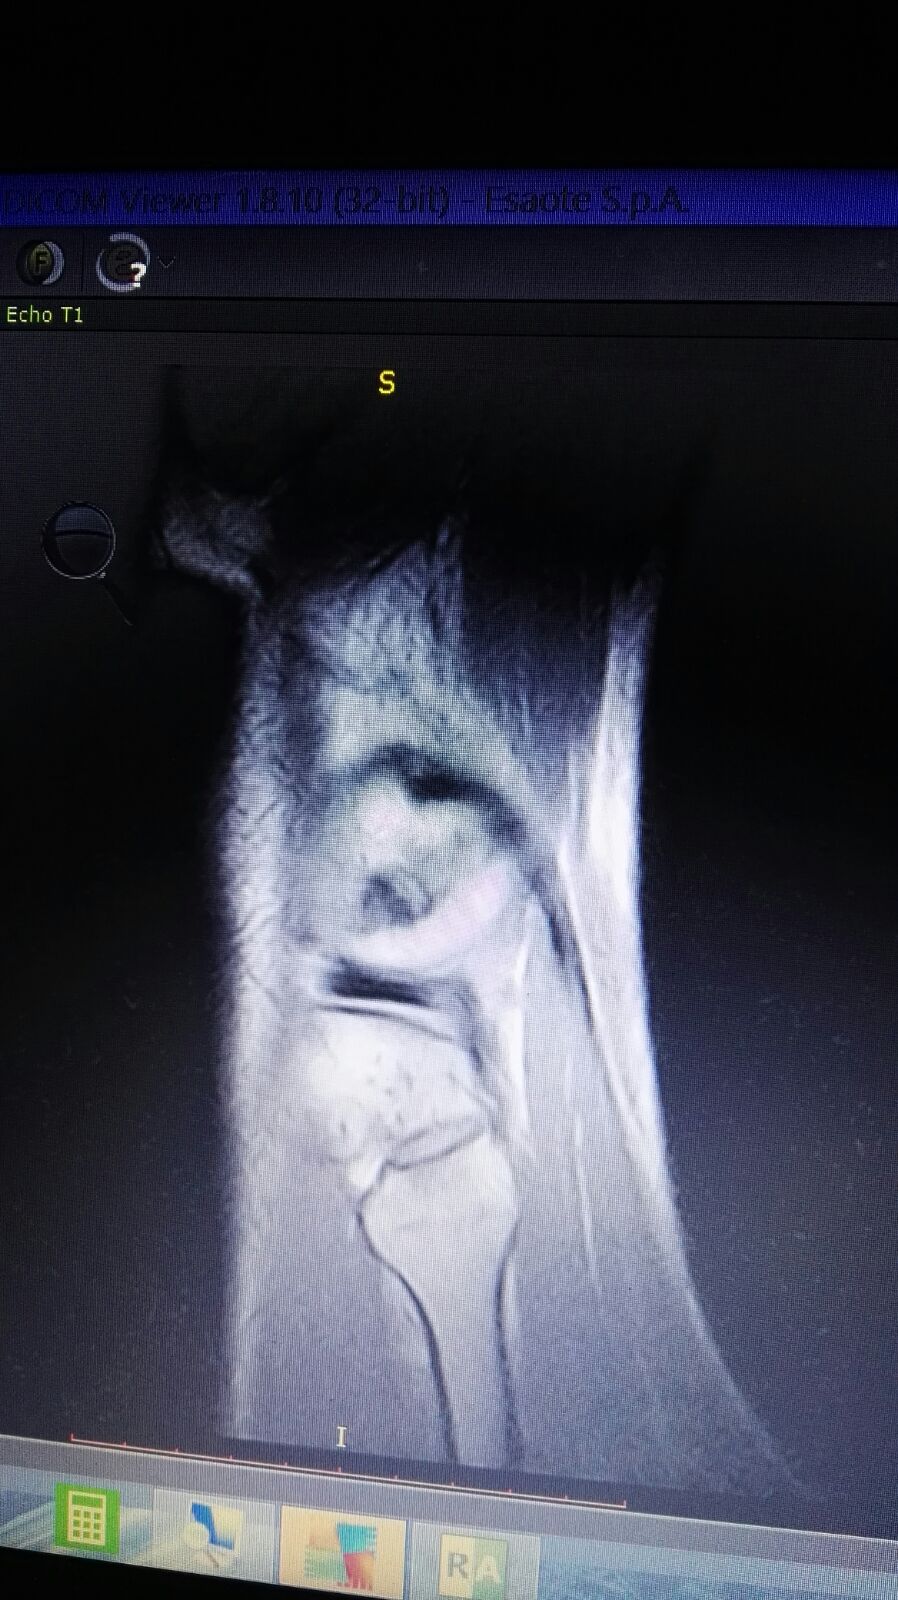

Salve mio marito circa un mese fa giocando a calcio si è fatto male il ginocchio. Essendo fuori per lavoro e riuscito solo a farsi una RSM LE mandi le foto se gentilmente può vederle. Lui è in addestramento per una missione volevo sapere se in un mese può farcela a guarire grazie mille.

IMG-20180301-WA0035.jpg

[ 168.58 KiB | Osservato 1320 volte ]